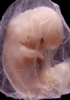

Most embryos at stage 19 are approximately 47-48 post-ovulatory days old and measure 17-20 mm in length. Distinguishing criteria for this stage include straightening of the trunk, the limbs extend nearly directly forward, toe rays are prominent, but interdigital notches have not yet appeared in the foot.

Although some of the photographs below show abnormal embryos, the animations and MRI slice images all depict normal embryos. Abnormal embryos are noted in the titles of the large photos when they are opened.

Photographs